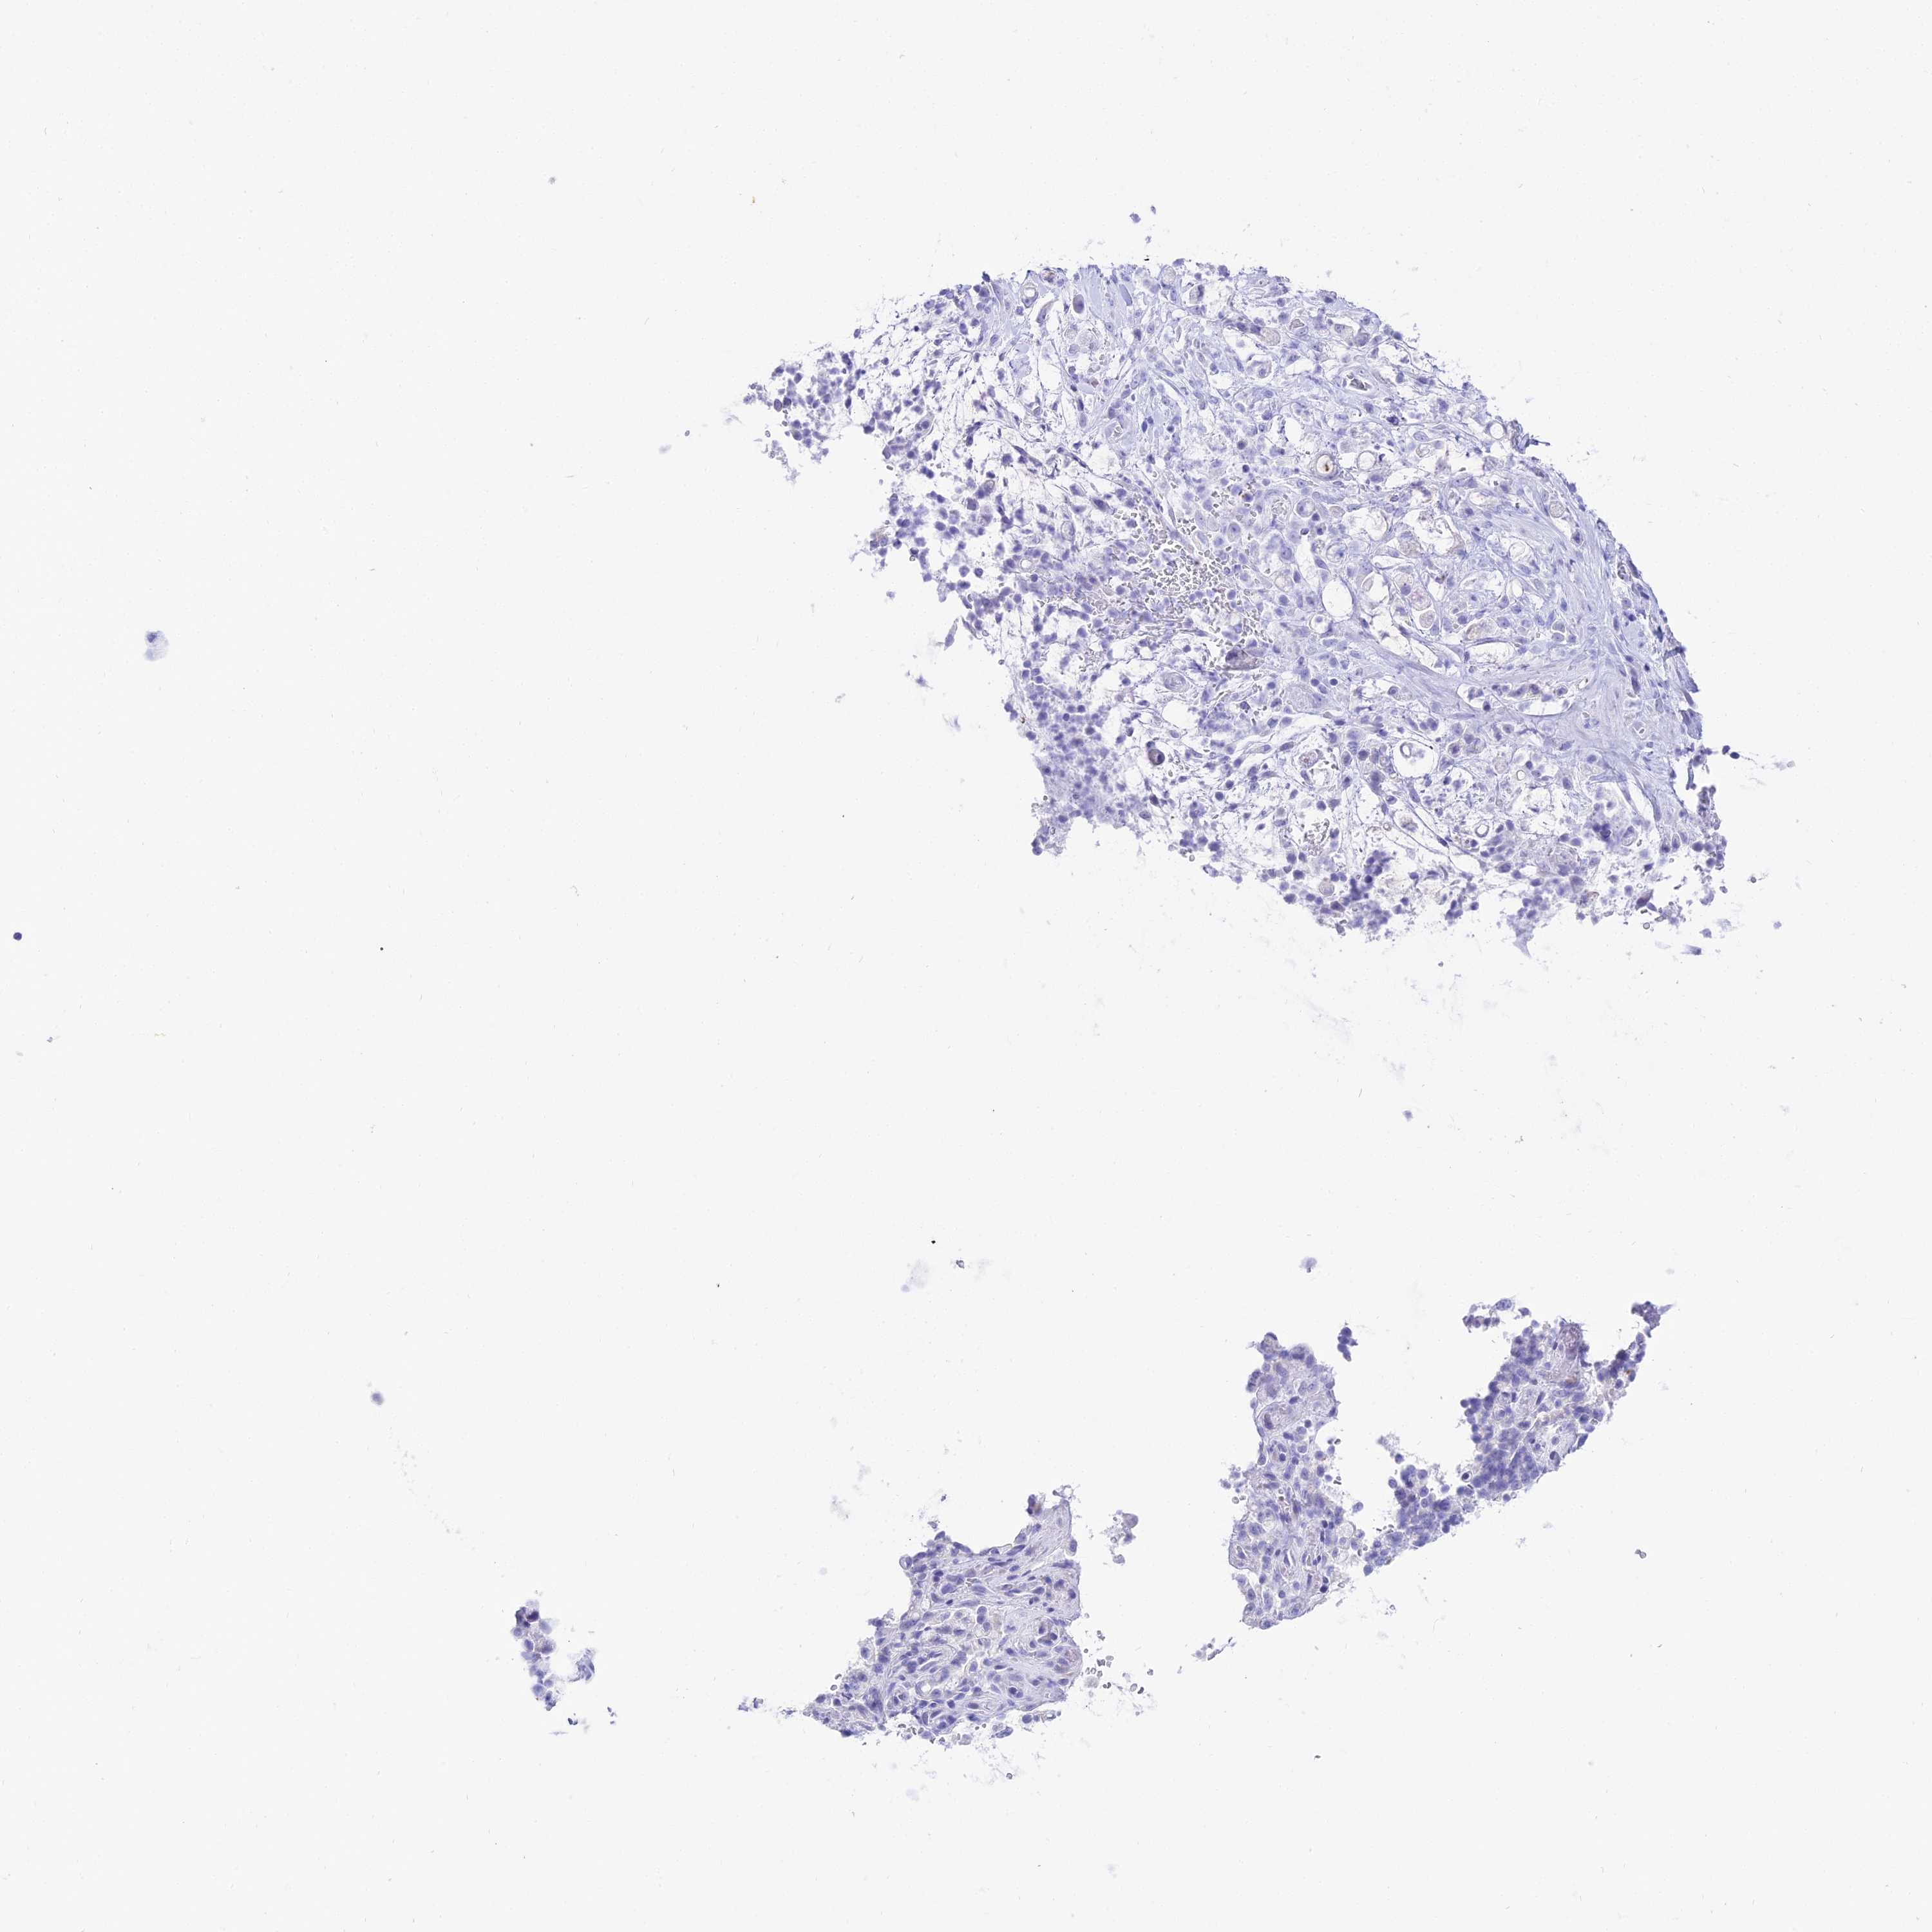

STOMACH CANCER - Protein expressioni

A mouse-over function shows sample information and annotation data. Click on an image to view it in a full screen mode. Samples can be filtered based on level of antibody staining by selecting one or several of the following categories: high, medium, low and not detected. The assay and annotation is described here.

Note that samples used for immunohistochemistry by the Human Protein Atlas do not correspond to samples in the TCGA dataset.

Antibody stainingi

Antibody staining in the annotated cell types in the current human tissue is reported as not detected, low, medium, or high, based on conventional immunohistochemistry profiling in selected tissues. This score is based on the combination of the staining intensity and fraction of stained cells.

Each image is clickable and will lead to virtual microscopy that enables deeper exploration of all samples and also displays staining intensity scores, fraction scores and subcellular localization as well as patient and tissue information for each sample.

Antibody HPA045461

Staining

High

Medium

Low

Not detected

Intensity

Strong

Moderate

Weak

Negative

Quantity

>75%

75%-25%

<25%

None

Location

Nuclear

Cytoplasmic/membranous

Cytoplasmic/membranous,nuclear

Adenocarcinoma, NOS